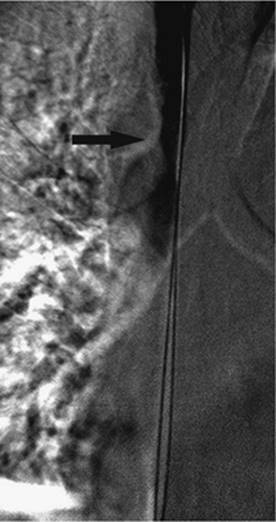

000431

Figure 35.14. Failed endoscopic placement of common bile duct (CBD) stent due to the presence of a large mass (black arrow) within the CBD. (Image courtesy of James Caridi, MD.)

000434

Figure 35.15. Successful percutaneous drainage using a left-sided biliary duct. Note that the drainage catheter has been advanced past the obstruction and into the small intestine. (Image courtesy of James Caridi, MD.)

000439

Figure 35.16. Patient presents with biliary obstruction. On hospital day 1, external drainage has been achieved using a right-sided bile duct approach. Cholangiogram shows complete obstruction in the mid common bile duct (CBD) (black arrow).

000443

Figure 35.17. On hospital day 2, internal/external drainage has been achieved by gaining access to the small intestine across the area of obstruction.